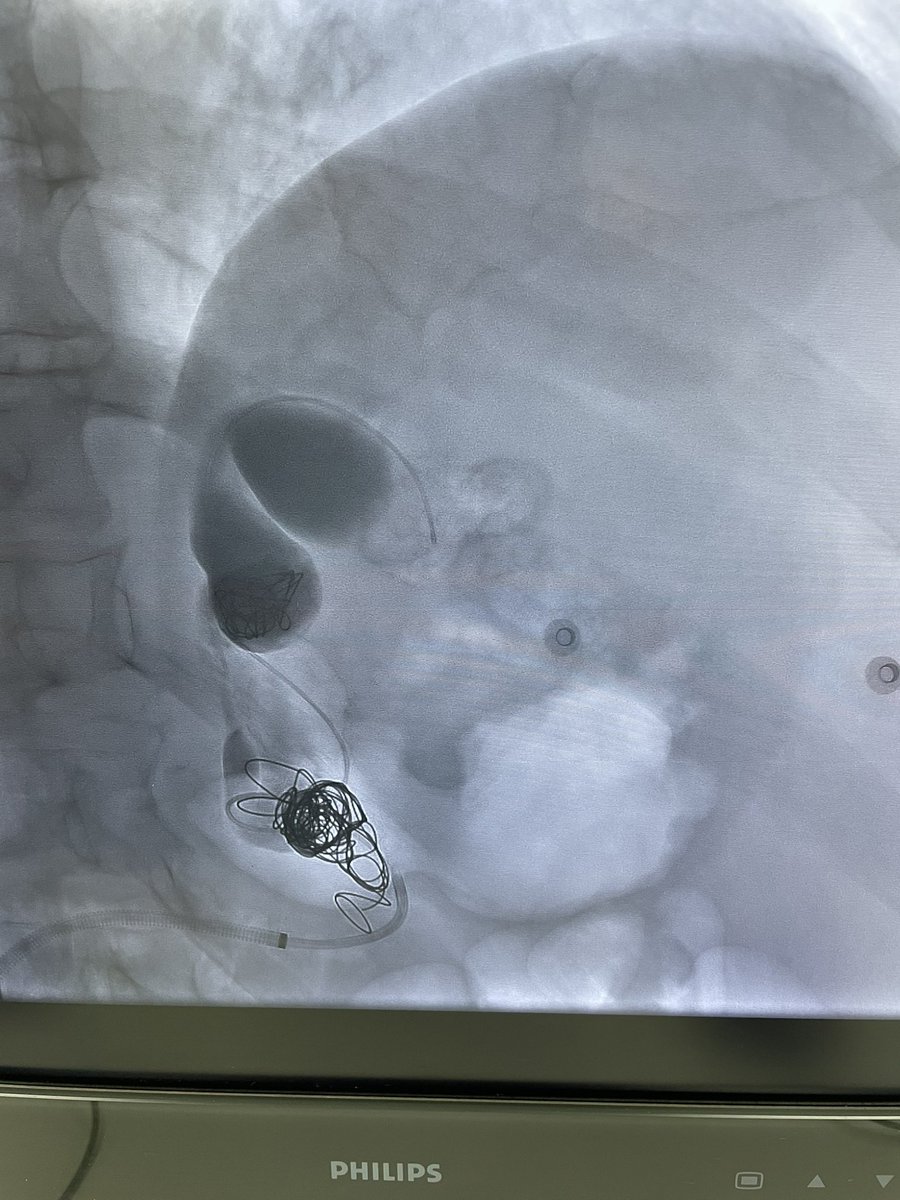

It is eventually here…took us 4 months to get this ready…lymphangiogram and glue embolization for lymphocele @SIRRFS @SIRspecialists @SIR_ECS @GESTSymposium @CVIR_Journal @RSNA @IR_UMMC @EmoryIRad @billmajdalany @JShaikhVIR youtu.be/yhUjBg-R46s